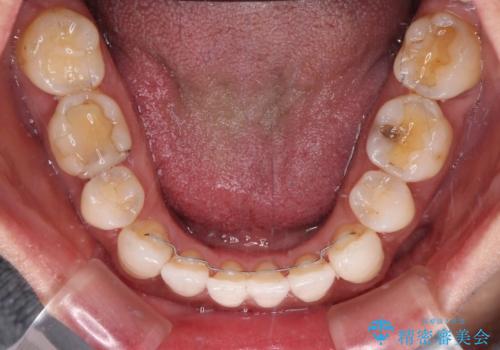

- 下顎前歯を中心に、以前行った矯正治療の後戻りが気になるとのことで来院された患者様です。

後戻りは軽度であったため、インビザライン・ライトにて治療を行うこととしました。

矯正治療後は、再度後戻りすることを極力回避するために、下顎前歯の舌側を細いワイヤーを用いて保定することとしました。